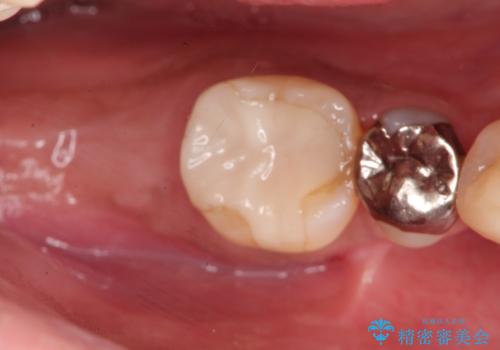

奥歯が痛い。骨増生を併用したインプラント

- 奥歯が痛いことを主訴に来院されました。

重度の歯周病により保存困難と診断し、抜歯後にインプラント治療を行いました。

抜歯後十分な骨の回復が認められず、単独の骨増生を行った後にインプラントを埋入しました。